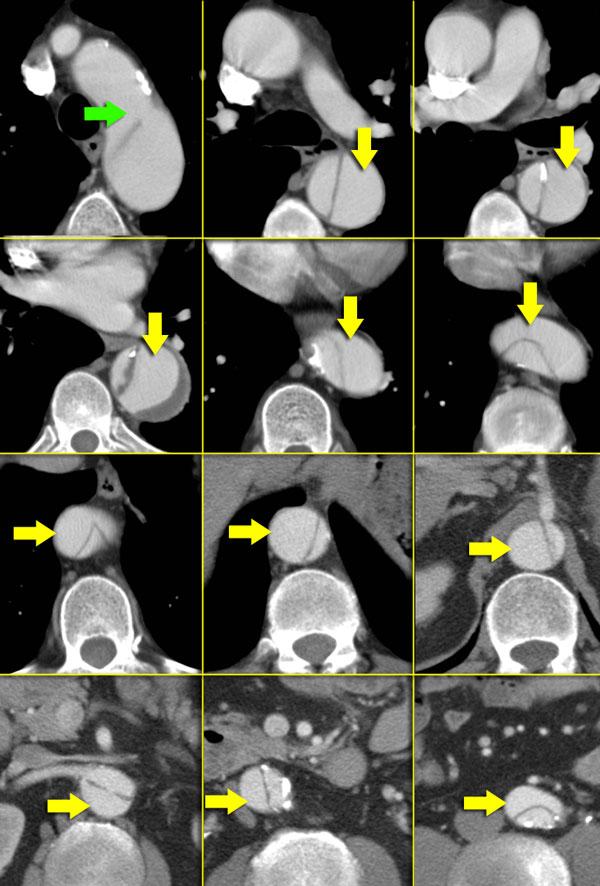

Bóc tách Type B. Mũi tên xanh lá chỉ điểm vào. Lòng giả được chỉ bởi các mũi tên vàng và thấy xoắn quanh lòng thật.

Đặc điểm hình ảnh

Trong bóc tách động mạch chủ, vạt nội mạc chỉ thấy trong 70% trường hợp.

Khi có 2 lòng mạch, chúng sẽ xoắn quanh nhau (hình minh họa).

Bên trái là các hình ảnh liên tiếp của một bóc tách Type B.

Lòng thật được bao quanh bởi các vôi hóa.

Lòng thật nhỏ hơn vì lòng giả chèn ép quanh lòng thật do áp lực tâm thu liên tục (gọi là dấu hiệu Mỏ chim – Beak-sign).

Huyết khối luôn nằm trong lòng giả, lòng này ngấm thuốc muộn hơn lòng thật.

Lòng thật:

- Được bao quanh bởi các vôi hóa (nếu có)

- Nhỏ hơn lòng giả

- Thường là nguồn gốc của thân tạng, động mạch mạc treo tràng trên (SMA) và động mạch thận phải

Lòng giả:

- Có dòng chảy hoặc bị tắc bởi huyết khối (mạn tính).

- Ngấm thuốc muộn

- Chèn ép quanh lòng thật (dấu hiệu mỏ chim)

- Các mảnh còn lại của lớp áo giữa dạng collagen (dấu hiệu mạng nhện – cobwebs)

- Lớn hơn lòng thật

- Cấu hình hình tròn (áp lực tâm thu liên tục)

- Bờ cong ngoài của quai động mạch chủ

- Thường là nguồn gốc của động mạch thận trái

- Bao quanh lòng thật trong bóc tách Type A

Bên trái thấy hình ảnh bóc tách động mạch chủ với lòng giả lớn.

Lòng thật bị chèn ép thấy ở phía trong và sáng hơn lòng giả.

Hình thành huyết khối trong lòng giả.

Lòng thật thường nhỏ hơn vì lòng giả chèn ép quanh lòng thật do áp lực tâm thu liên tục.

Lòng giả thường bám vào bờ cong ngoài của quai động mạch chủ, như thấy trong trường hợp này.

Các mảnh còn lại của lớp áo giữa dạng collagen (dấu hiệu mạng nhện) chỉ thấy trong lòng giả.

Điều tương tự cũng đúng với huyết khối.

Nếu một trong các lòng mạch bị bao quanh bởi lòng kia, thì đó chắc chắn là lòng thật.

Điều này hầu như chỉ xảy ra trong bóc tách type A.

Các hình ảnh bên trái đều cho thấy bóc tách type A với điểm vào rõ ràng ở động mạch chủ lên.

Lòng thật được bao quanh bởi lòng giả, lòng giả lớn hơn và chèn ép quanh lòng thật do áp lực tâm thu liên tục.